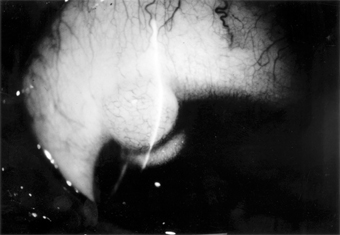

1. Hyperacute (and subacute) bacterial conjunctivitis-Purulent conjunctivitis-

(caused by N gonorrhoeae, Neisseria kochii, and N meningitidis) is marked by a profuse purulent exudate (Figure 5-1). Meningococcal conjunctivitis may occasionally be seen in children. Any severe, profusely exudative conjunctivitis demands immediate laboratory investigation and immediate treatment. If there is any delay, there may be severe corneal damage or loss of the eye, or the conjunctiva could become the portal of entry for either N gonorrhoeae or N meningitidis, leading to septicemia or meningitis.

Figure 5-1

Figure 5-1: Gonococcal conjunctivitis. Profuse purulent exudate. (Courtesy of L Schwab.)